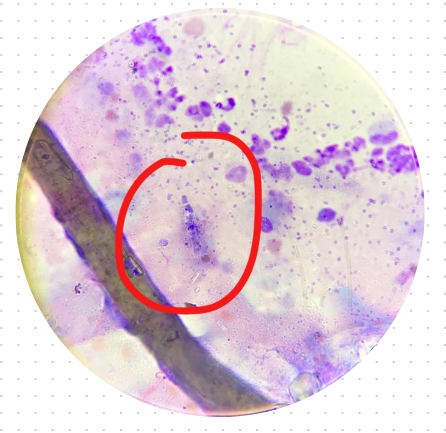

2.皮肤刮片镜检:通过拔取毛根或皮屑,在显微镜下观察菌丝和孢子,准确率达90%以上。